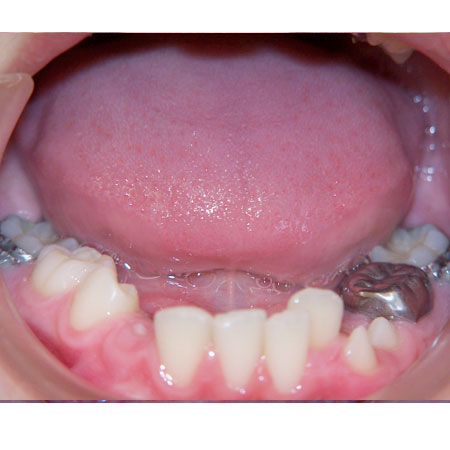

APIÑAMIENTO INFERIOR